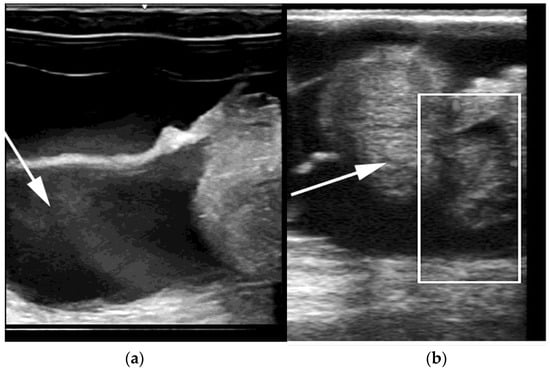

Segmental aplasia can affect any part of the tubular genitalia. An imperforate (persistent) hymen is the most common of these abnormalities. Affected females are presented with discomfort or tenesmus during mating. Transrectal ultrasonography reveals mucocolpos and mucometra (Figure 2). Other forms of segmental aplasia of the tubular genitalia include vaginal aplasia, uterus unicornis, and congenital hydrosalpinx due to segmental aplasia of the uterine tube (Figure 3) [6,7,14,28].

Figure 2. Ultrasonograms of mucometra due to an imperforate hymen in an alpaca. (a) cranial vagina (arrow); (b) cervical os (arrow) and uterine body.